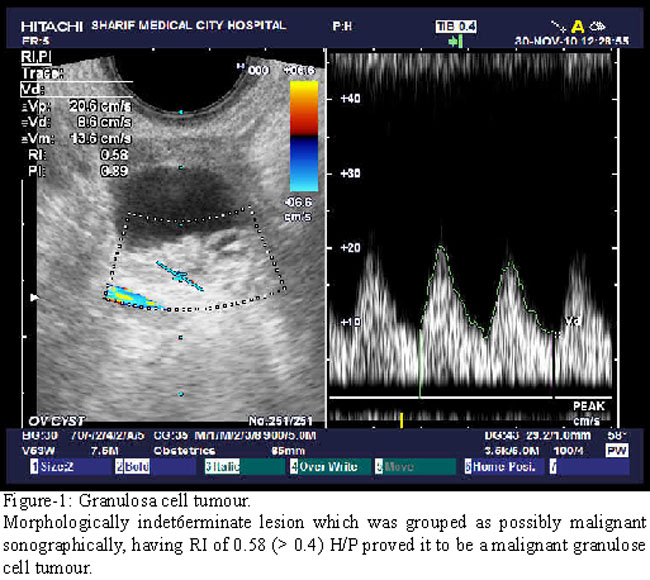

A total of 37 masses were examined transabdominally with a 3.5-MHz transducer and transvaginally with a 5-MHz transducer with Doppier capability. All sonograms were obtained with Hitachi 5500. Color Doppler imaging was used to guide placement of the Doppler gate for pulsed Doppler analysis. RI (RI = [peak systolic velocity - end diastolic velocity]/peak systolic velocity) was calculated for any vessel at the periphery or within the mass. Sonograms were evaluated by two experienced sonologists. The size, echogenicity, wall thickness, and presence of septations and endocystic vegetations were determined for each mass. The lesions were classified as benign, indeterminate, or malignant. Morphologically, benign lesions had the classic appearance of a simple cyst (anechoic with a thin wall and acoustic enhancement, with or without a single thin septation), a dermoid (cyst with fluid layer or echogenic mural nodule with shadowing), or an endometrioma (cyst with diffuse low-level echoes with one or two thin septations and a thin wall. Indeterminate lesions had a predominantly benign appearance with atypical features such as a thick wall or thick, multiple, or irregular septations (Fig. 1). Morphologically malignant lesions had nodules or solid elements. For statistical purposes, lesions deemed indeterminate and malignant were grouped together as possibly malignant. Surgical pathologic reports for 37 lesions were reviewed. SPSS version 17 was used to configure the data.

The mean of the lowest recorded RI for the benign lesions was 0.56 ± 0.14 (range, 0.32-0.8). The mean lowest RI for malignant lesions was 0.52 ± 0.11 (range, 0.35-0.7). Nineteen lesions were morphologically benign on sonograms and pathology revealed all these to be benign. The RI was greater than 0.4 in 15 of these 1 9 cases. Three endometriomas had low RIs of 0.32, 0.36, and 0.37. Eight lesions could not be characterized properly and were considered as indeterminate lesions. Histopathology, revealed that 5, out of these 8 lesions, were endometriomas, and 2 were cystadenomas and one was a cystic granulosa cell tumour. The RI was greater than 0.4 in six of the seven that were benign and in the granulosa cell tumour. The RI was 0.32 in one endometrioma. Ten lesions were characterized as malignant on the basis of sonographic features. Pathologic examination showed that eight of the 10 were malignant. The other two were ruptured cysts with haemorrhage and inflammation. The RI was less than 0.4 in two of the eight malignant lesions with malignant morphology. It was greater than 0.4 in the other seven malignant and two benign lesions in this category (Figure-1&2).